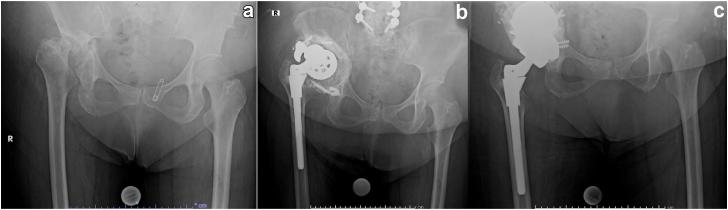

Trabecular metal augments (TMAs) have been extensively used in revision total hip arthroplasty (THA) to address acetabular bone defects. However, limited data exists regarding TMA utilization during primary THA. This study aims to assess the clinical and radiographic outcomes of TMAs used during primary THA.

Twenty-six patients (30 hips) were included with average age of 52.6 ± 15.3 years (range: 22-78) and mean follow-up of 4.1 ± 2.1 years (range: 2.0-8.9). Most TMAs were indicated for developmental dysplasia of the hip (n = 18; 60.0%). On average, hip center of rotation was lowered 1.5 ± 1.3 cm and lateralized 1.2 ± 1.5 cm, while leg length and global offset were increased by 2.4 ± 1.2 cm and 0.4 ± 1.0 cm, respectively. At final follow-up, 3 hips (10.0%) required revision: one (3.3%) for aseptic loosening and 2 (6.7%) for instability. No patients had progressive radiolucent lines at final follow-up. Five-year survival with aseptic loosening and all-cause revision as endpoints was 100% (95% confidence interval: 90.0%-100.0%) and 92.1% (95% confidence interval: 81.3%-100.0%), respectively. One patient required revision for aseptic loosening after the 5-year mark.

小梁金属增强物(TMA)已广泛应用于翻修全髋关节置换术(THA)以处理髋臼骨缺损。然而,关于初次THA期间TMA使用的数据有限。本研究旨在评估初次THA期间使用TMA的临床和影像学结果。

纳入26例患者(30髋),平均年龄52.6±15.3岁(范围:22 - 78岁),平均随访4.1±2.1年(范围:2.0 - 8.9年)。大多数TMA用于髋关节发育不良(n = 18;60.0%)。平均而言,髋关节旋转中心降低1.5±1.3 cm,向外移位1.2±1.5 cm,而肢体长度和整体偏移分别增加2.4±1.2 cm和0.4±1.0 cm。在末次随访时,3髋(10.0%)需要翻修:1髋(3.3%)因无菌性松动,2髋(6.7%)因不稳定。在末次随访时,没有患者出现进展性透亮线。以无菌性松动和全因翻修为终点的5年生存率分别为100%(95%置信区间:90.0% - 100.0%)和92.1%(95%置信区间:81.3% - 100.0%)。1例患者在5年标记之后因无菌性松动需要翻修。